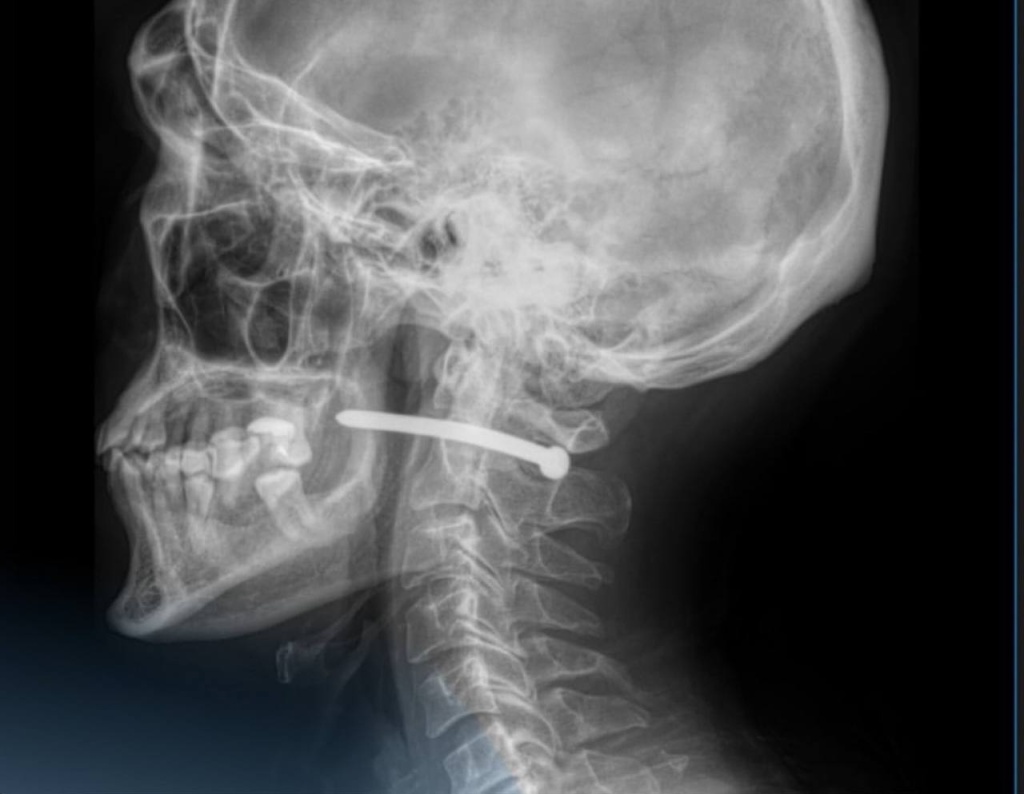

В Петропавловске хирурги удалили гвоздь от пневмопистолета, который попал в шею жителя по неосторожности. Врачи больницы говорят, что ему чудом повезло, важные органы не задеты.